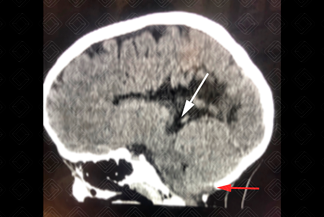

Descrição da imagem: Tomografia computadorizada do crânio com reconstrução sagital, confirmando achados característicos da malformação de Chiari tipo 2. Observa-se o mesencéfalo em bico (seta branca), o deslocamento do vérmis cerebelar através do forame magno (seta vermelha) e o cerebelo em torre.

• Ressonância magnética do crânio: C erebelo em "torre"→ compressão do mesencéfalo com o teto mesencefálico em "bico", quarto ventrículo alongado sem ápice posterior (fastígio), disrafismo espinhal aberto (mielomeningocele) → 100% dos casos, sendo mais comum na coluna lombar seguida da cervical.